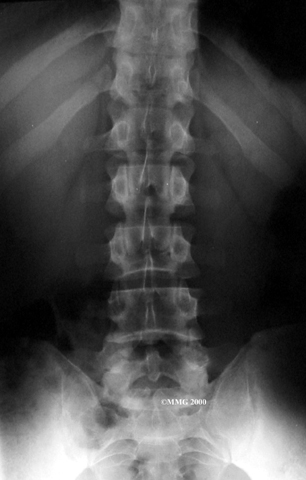

The human spine is formed by 24 spinal bones, called vertebrae. Vertebrae are stacked on top of one another to form the spinal column. The spinal column gives the body its form. It is the body's main upright support. The section of the spine in the lower back is known as the lumbar spine.

The lumbar spine is made up of the lower five vertebrae. Doctors often refer to these vertebrae as L1 to L5. These five vertebrae line up to give the low back a slight inward curve. The lowest vertebra of the lumbar spine, L5, connects to the top of the sacrum, a triangular bone at the base of the spine that fits between the two pelvic bones. Some people have an extra, or sixth, lumbar vertebra. This condition doesn't usually cause any particular problems.